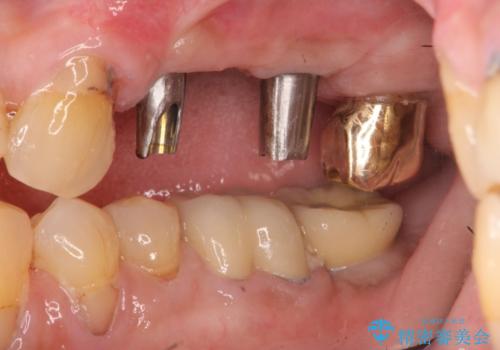

- 奥歯を失い半年間入れ歯を使用してみたが、とにかく咬めない、食事を楽しむことができない!と

咬合機能の回復を求めて来院されました。

しっかりとまた物を噛めるようになるために、インプラントを用いて咬合機能を回復していきます。

- 106.7万円(インプラント×2・チタンカスタムアバットメント×2・ジルコニアクラウン×3・仮歯×3)費用は治療当時の料金となります